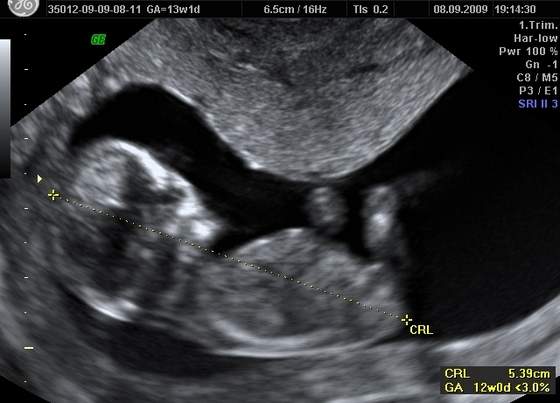

to moja kruszynka w 12 tygodzniu (troche spóźniałam się z wklejeniem)

śmieszne to zdjęcie, bo dzidziuś ma KOKA na głowieśmieje się, że to musi być dziewczynka